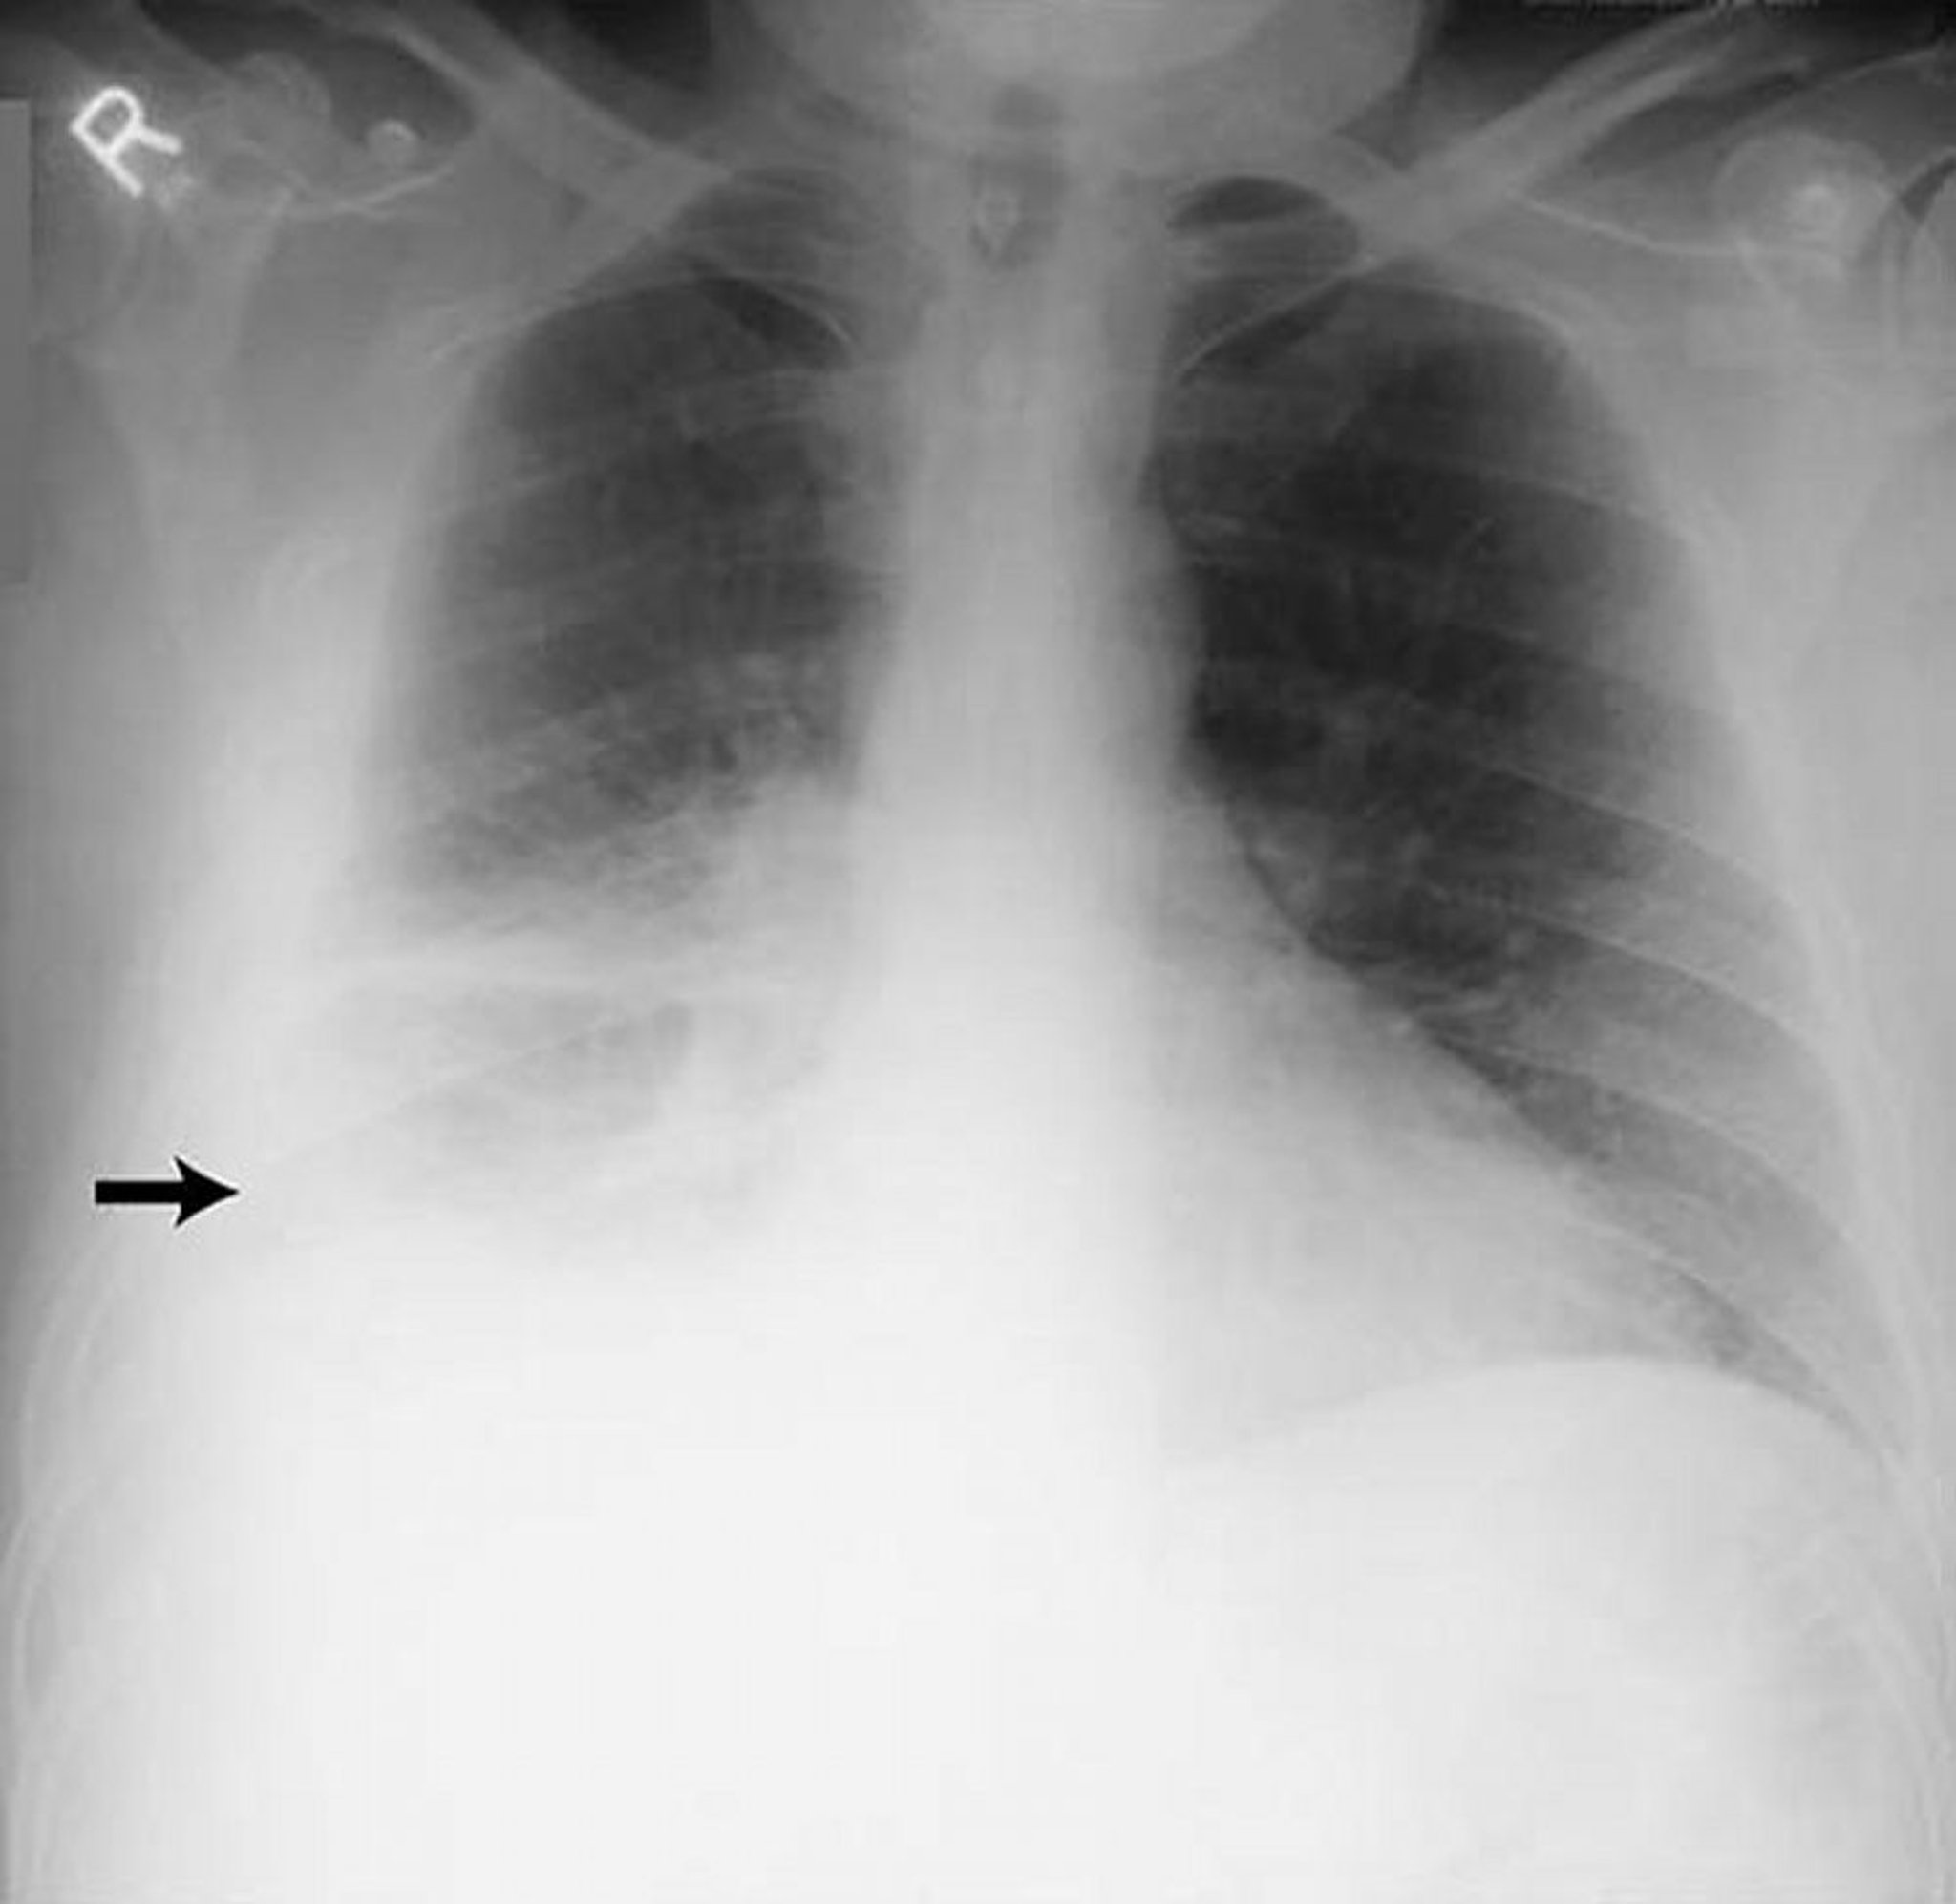

Pleural Effusion—Large

This image shows large right-sided pleural effusion (arrow) in a patient with rheumatoid pleuritis.

By permission of the publisher. From Huggins J, Sahn S. In Bone's Atlas of Pulmonary and Critical Care Medicine. Edited by J Crapo. Philadelphia, Current Medicine, 2005.